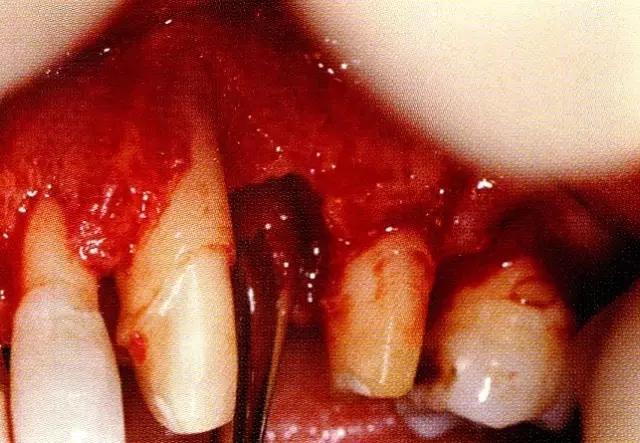

病例4  針對連續(xù)性骨缺損,利用2張非吸收性膜進(jìn)行再生治療的病例。

▲圖8-3  進(jìn)行全厚瓣翻瓣,將根表面的沉積物、骨缺損的肉芽組織徹底清除,確認(rèn)牙槽骨形態(tài),可看到從頰側(cè)到遠(yuǎn)中存在垂直性和水平性的骨缺損。